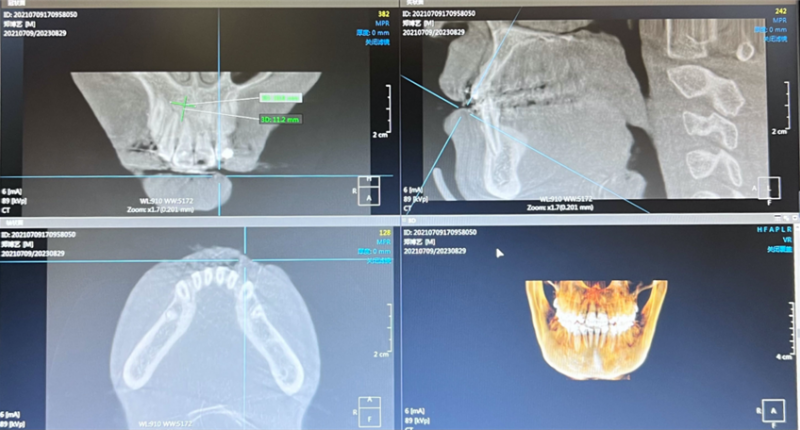

术后口腔CBCT。(翻拍图片)

巫山县中医院口腔科常樨林主任与烟台山医院支医专家田鸿旭医生对患者的临床资料和影像学资料进行了详细分析,确定了“11牙根管治疗+根端囊肿摘除术+位点保存术+引导骨再生手术”的治疗方案。在征得患者及其家长的同意后,田鸿旭医生主刀,为患者实施了“11牙根管治疗+根端囊肿摘除术+位点保存术+引导骨再生手术”。手术过程顺利,术后即刻CBCT检查显示:根端囊肿完全清除且骨填充致密。术后10天,患者的创区愈合良好,顺利拆线。